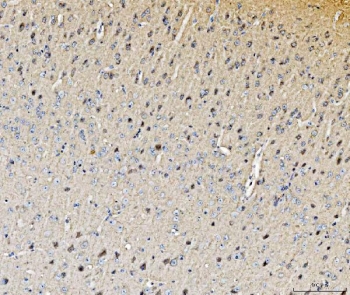

IHC staining of FFPE mouse brain tissue with Histidine decarboxylase antibody. HIER: boil tissue sections in pH8 EDTA for 20 min and allow to cool before testing.